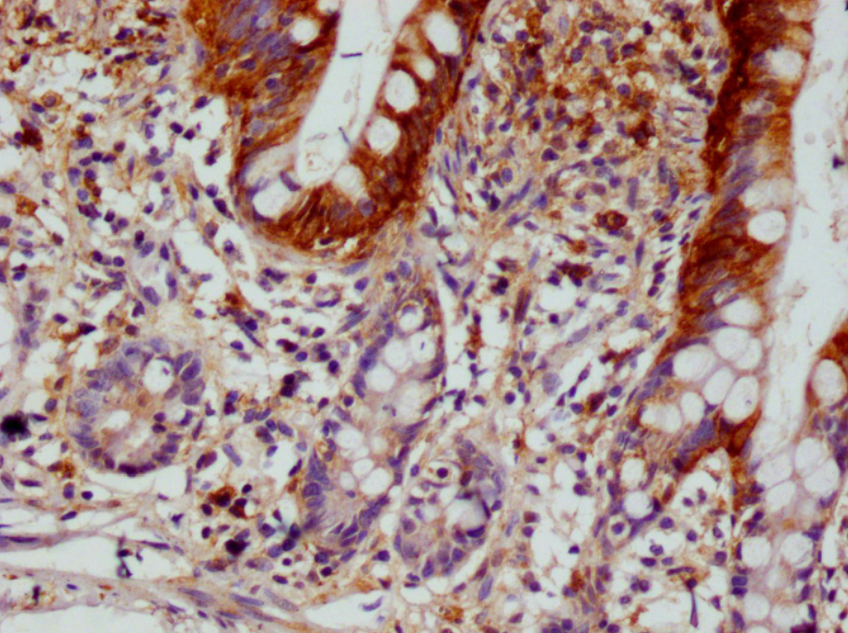

IHC圖像說明

SCIN重組單克隆抗體稀釋度為1:100,在Leica Bond系統(tǒng)上對石蠟包埋的人小腸組織進行染色。脫蠟和水化后,通過在檸檬酸緩沖液(pH 6.0)中高壓處理進行抗原修復(fù)。切片用10%正常山羊血清在室溫下封閉30分鐘,然后用1% BSA的初級抗體在4℃下孵育過夜。初級抗體通過辣根過氧化物酶標(biāo)記的山羊抗兔聚合IgG檢測,并使用0.05% DAB進行顯色。